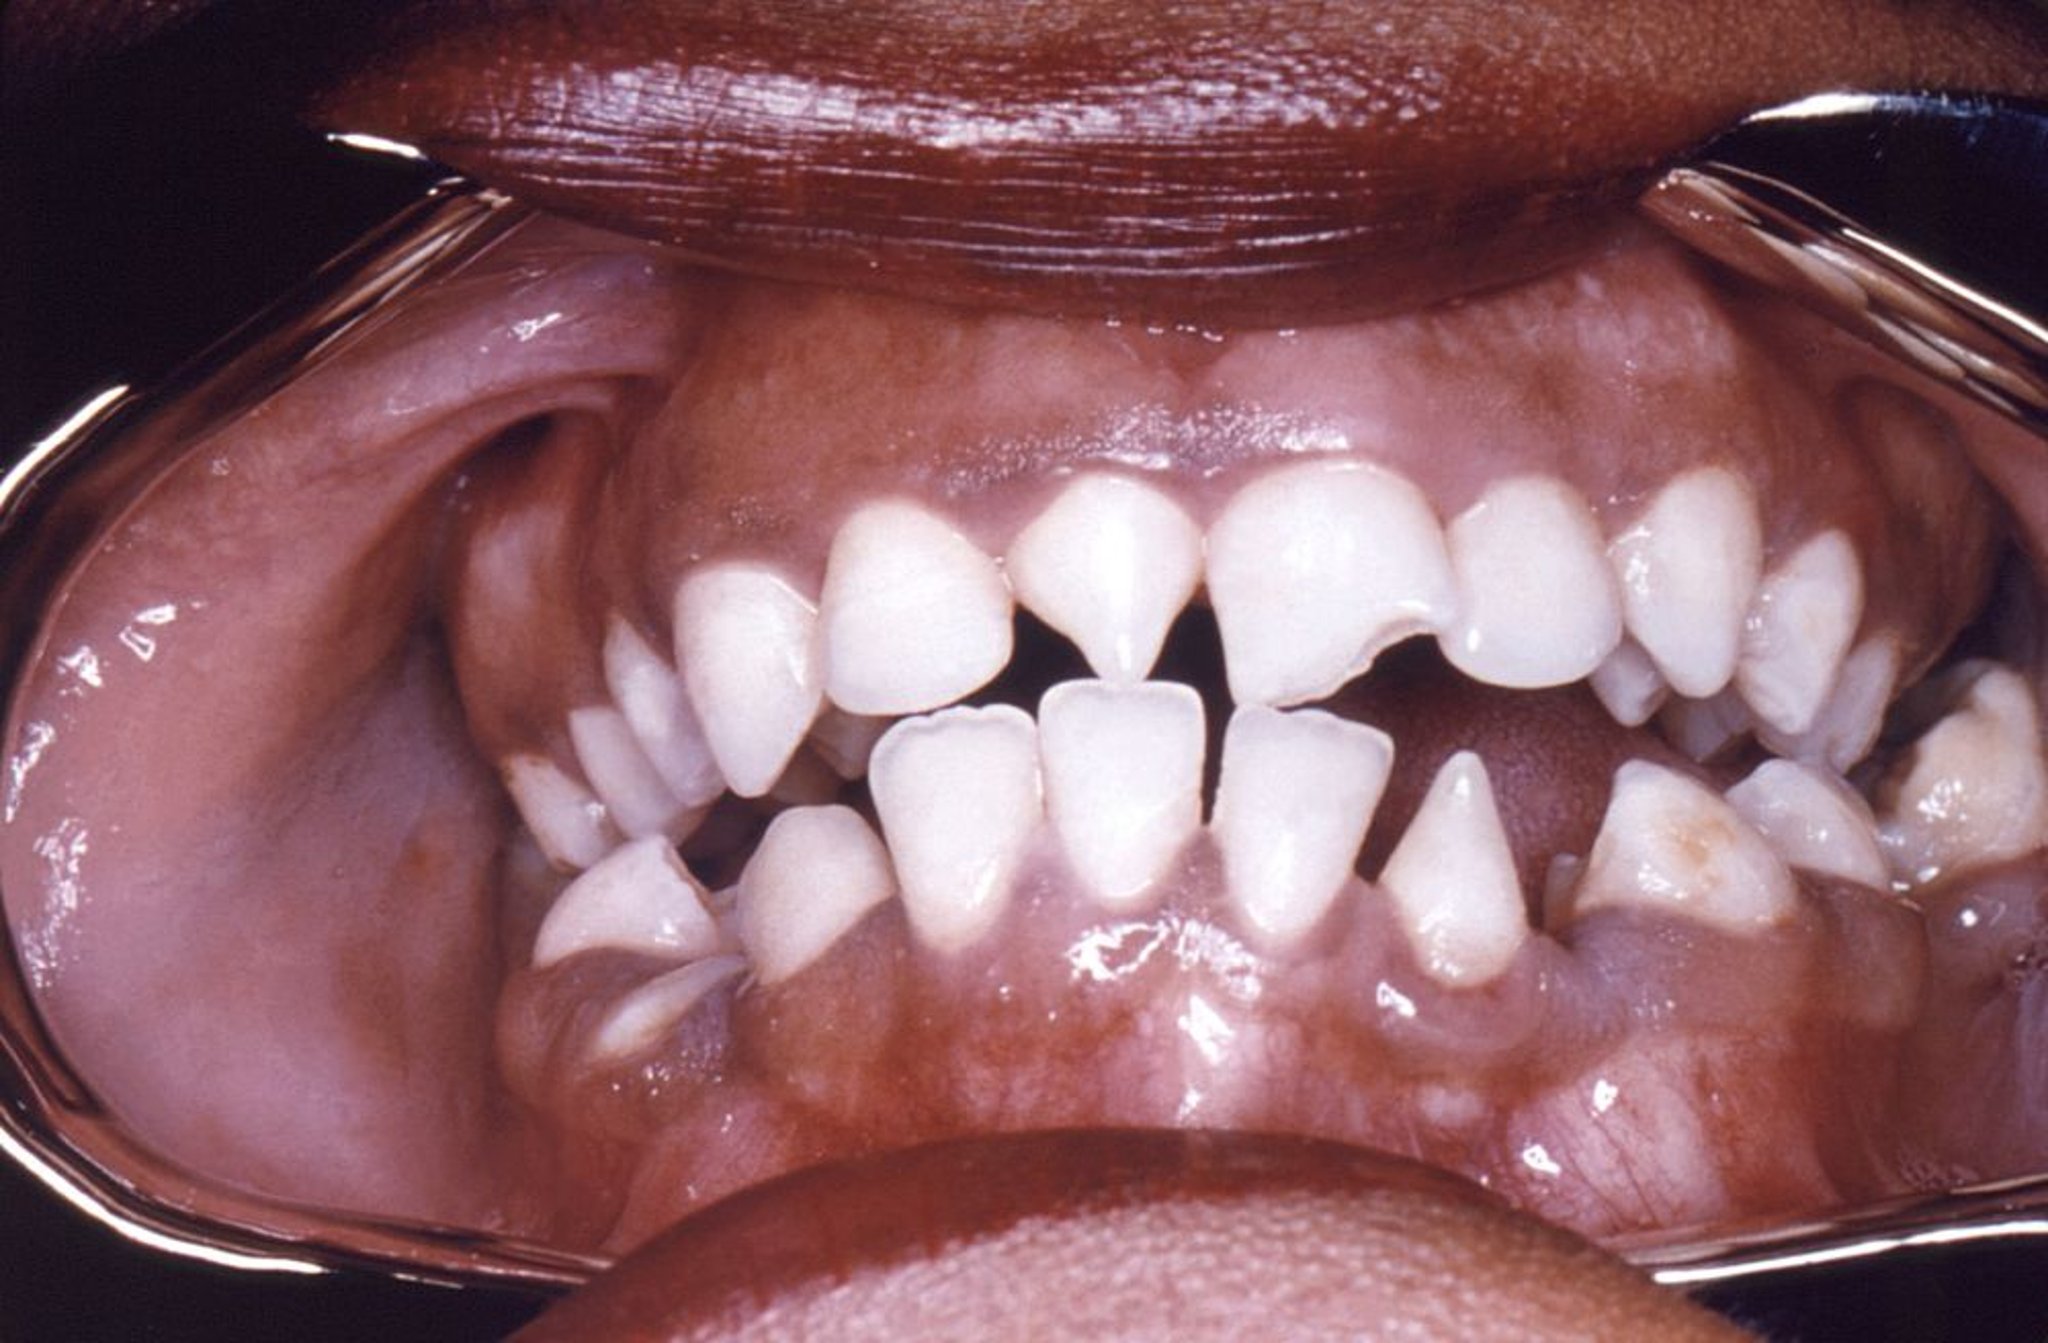

Зубы Гетчинсона

Эта фотография показывает деформацию в форме треугольника правых верхних и левых нижних резцов, вызванную врожденным сифилисом.